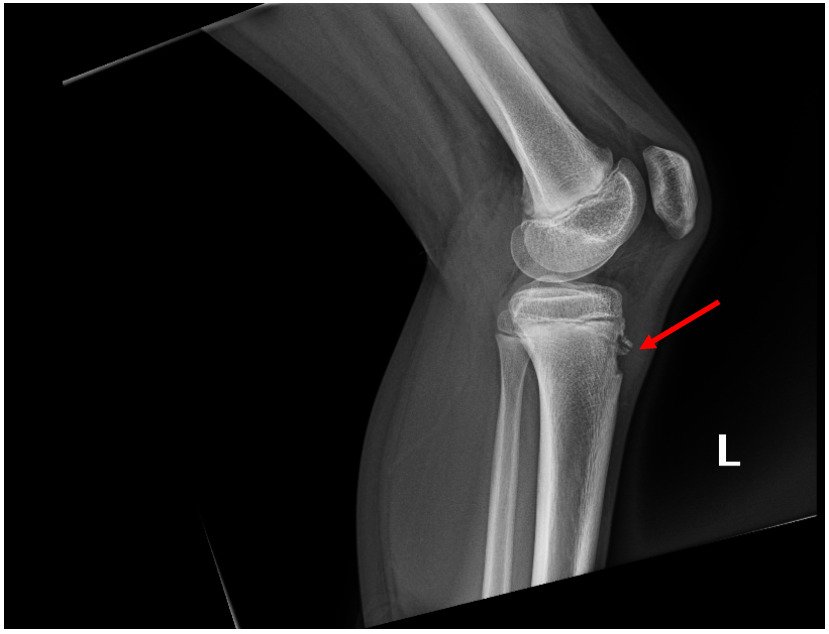

A 10-year-old female came into the emergency department (ED) after complaining about atraumatic knee pain and pressure. The patient had been very active, ran daily, and was slender. She was not unwell in any way and denied any fever, chills, chest pain, shortness of breath, headaches, or urinary problems. A physical examination was conducted and the following signs were found: pulse oximetry levels of 99% on room air, body temperature of 98.0 degrees, a pulse rate of 101 beats per minute, a respiratory rate of 18 breaths per minute, and significant pain at the tibial tubercle. Due to the tenderness of the patella, an X-ray of the knee was ordered. The knee radiograph demonstrated a small growth at the tibial tubercle (Figures 1 and 2). This growth was pressing against the shinbone and was the likely cause of pain for the patient.